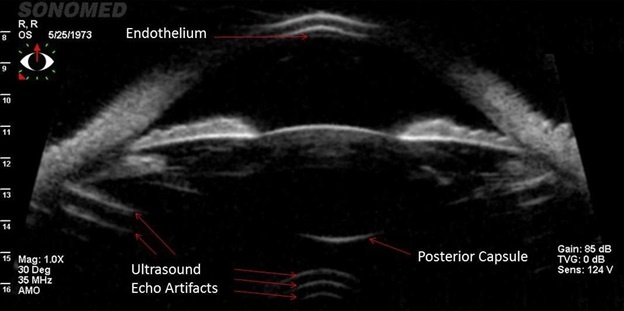

По мере старения организма, резервные способности аккомодации постепенно снижаются. Так, согласно данным Дондерса, у пациентов с нормальным зрением в 20 лет он составляет около 10 диоптрий, в 50 снижается до 2,5 диоптрий, а к 55 года – до 1,5 диоптрий. Существуют современные приборы, которые в автоматическом режиме измеряют статическую рефракцию и динамическую рефракцию (аккомодацию). А «вживую» этот процесс мы можем наблюдать при проведении УБМ (ультразвуковой биомикроскопии), где мы наблюдаем состояние хрусталика и его связок.